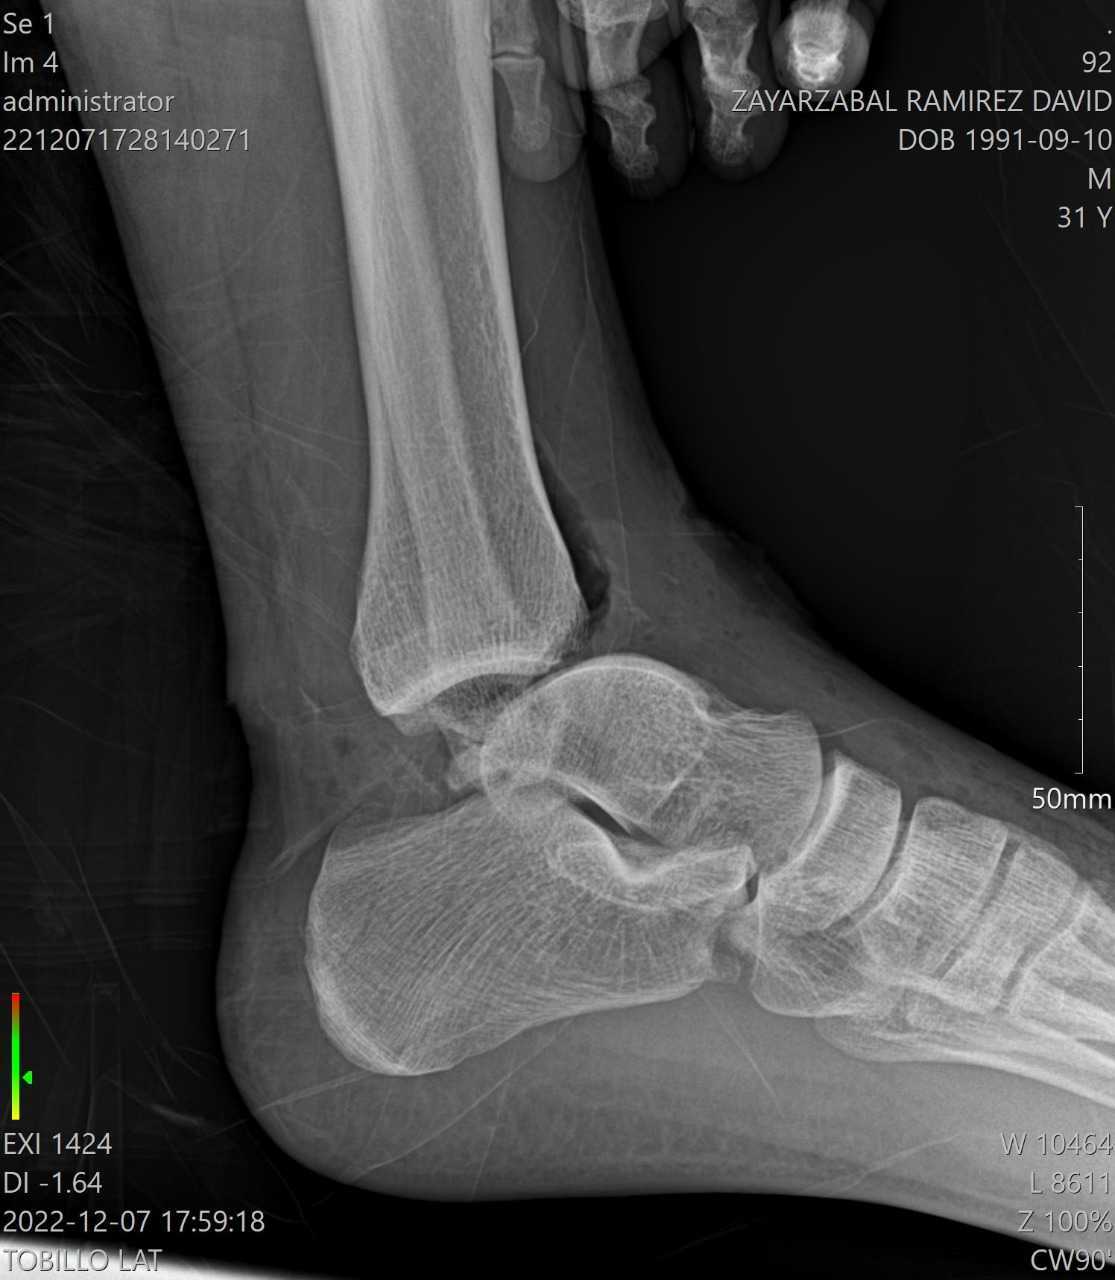

Esto le provocó múltiples heridas en su rodilla y pie izquierdo, por lo que testigos llamaron al 911 para pedir ayuda de las autoridades y atención médica, por lo que al lugar acudieron peritos para mediar la situación.